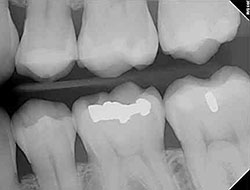

Digital X-Rays

x-rayUsing the most advanced dental technology possible is just as important as staying up-to-date on the latest treatment techniques. Because our practice is dedicated to providing you with the safest and most convenient treatment options available, we utilize advanced digital X-ray technology in our office.

Digital X-rays provide several advanced imaging options that are designed to save time, provide clearer dental photos, and expose patients to less radiation than with traditional X-ray technology.